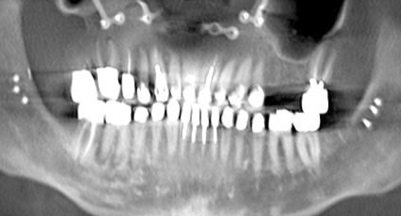

Interceptive implant therapy may then become a consideration earlier in life to create restorations that will not be subject to the latent effect of dental caries as aging continues. An example is shown in Figure 6 and Figure 7; the panoramic film of a 56-year-old man shows several orthognathic and extensive dental procedures historically. All full-coverage restorations had been replaced for a second time, and, again, all evidenced recurrent caries, but the existing dentition was periodontally sound and relatively esthetic.

Fig 6. Panoramic radiograph of 56-year-old patient illustrating a number of dental procedures historically.

Figure 6